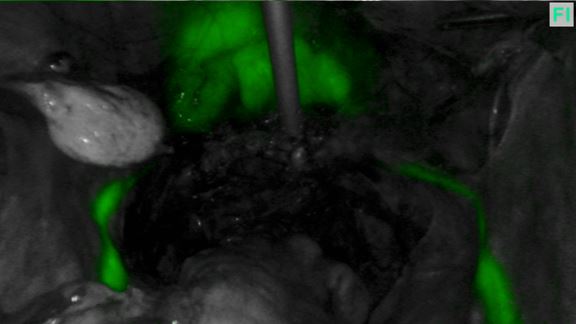

Figure 1A

Path of ureters at the start of endometriosis surgery

Figure 1B

In the past I often had to dissect out the ureter and place a rubber sloop or even consider a ureteric stent but both of these procedures can cause trauma to the ureter. However slooping will only help identifying a portion of the ureter whereas ICG can show the entire length of pelvic ureter (figures 1A and 1B below). Stenting can lead to post-operative pain and haematuria and I don’t find them particularly helpful in identifying the ureter prior to seeing the stent when you transect the ureter!